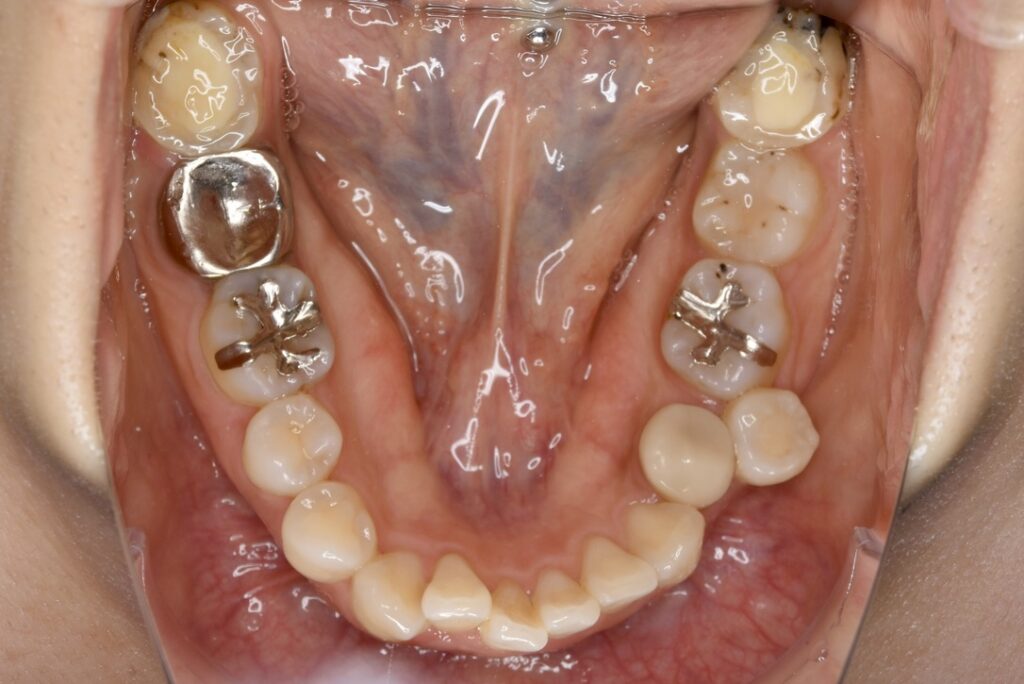

32歳 女性 治療期間:1年7ヶ月

BEFORE

診断名・主な症状 叢生を伴う上顎前突

治療内容 上下とも歯を2本抜いて、上の前歯を後方に引きながら、でこぼこを治しました。

抜歯部位 上 両側4番目

下 右側4番目、左側5番目